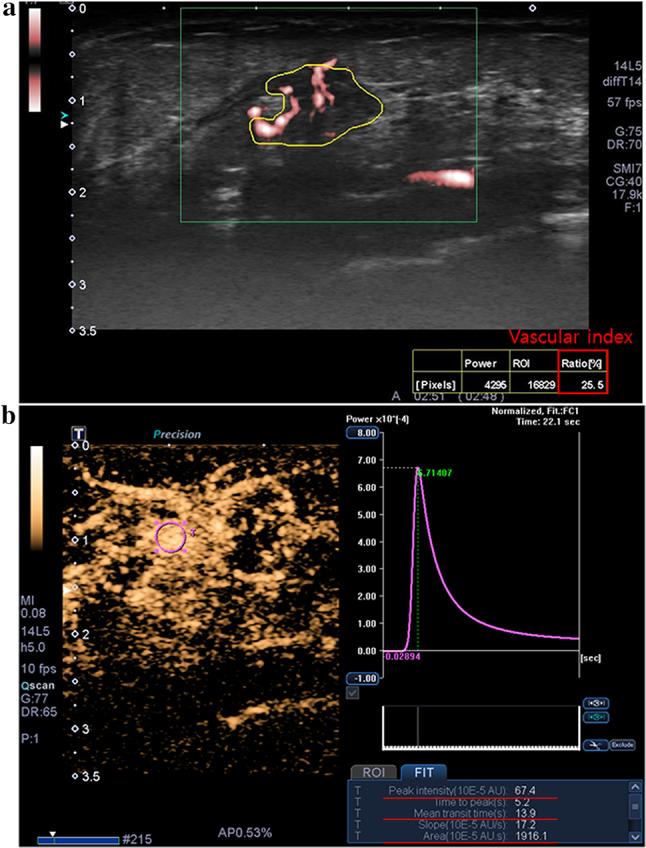

There are few radiogenomic studies to correlate ultrasound features of breast cancer with genomic changes. We investigated whether vascular ultrasound phenotypes are associated with breast cancer gene profiles for predicting angiogenesis and prognosis. We prospectively correlated quantitative and qualitative features of microvascular ultrasound (vascular index, vessel morphology, distribution, and penetrating vessel) and contrast-enhanced ultrasound (time-intensity curve parameters and enhancement pattern) with genomic characteristics in 31 breast cancers. DNA obtained from breast tumors and normal tissues were analyzed using targeted next-generation sequencing of 105 genes. The single-variant association test was used to identify correlations between vascular ultrasound features and genomic profiles. Chi-square analysis was used to detect single nucleotide polymorphisms (SNPs) associated with ultrasound features by estimating p values and odds ratios (ORs). Eight ultrasound features were significantly associated with 9 SNPs (p < 0.05). Among them, four ultrasound features were positively associated with 5 SNPs: high vascular index with rs1136201 in ERBB2 (p = 0.04, OR = 7.75); large area under the curve on contrast-enhanced ultrasound with rs35597368 in PDGFRA (p = 0.04, OR = 4.07); high peak intensity with rs35597368 in PDGFRA (p = 0.049, OR = 4.05) and rs2305948 in KDR (p = 0.04, OR = 5.10); and long mean transit time with rs2275237 in ARNT (p = 0.02, OR = 10.25) and rs755793 in FGFR2 (p = 0.02, OR = 10.25). We identified 198 non-silent SNPs in 71 various cancer-related genes. Vascular ultrasound features can reflect genomic changes associated with angiogenesis and prognosis in breast cancer.

很少有放射基因组学研究将乳腺癌的超声特征与基因组变化联系起来。我们研究了血管超声表型是否与乳腺癌基因谱相关,以预测血管生成和预后。我们前瞻性地将微血管超声的定量和定性特征(血管指数、血管形态、分布和穿入血管)以及超声造影(时间-强度曲线参数和增强模式)与31例乳腺癌的基因组特征进行了关联分析。使用针对105个基因的靶向二代测序分析从乳腺肿瘤和正常组织中获取的DNA。采用单变量关联检验来确定血管超声特征与基因组图谱之间的相关性。使用卡方分析通过估计p值和比值比(OR)来检测与超声特征相关的单核苷酸多态性(SNP)。八个超声特征与9个SNP显著相关(p < 0.05)。其中,四个超声特征与5个SNP呈正相关:血管指数高与ERBB2基因中的rs1136201相关(p = 0.04,OR = 7.75);超声造影下曲线下面积大与PDGFRA基因中的rs35597368相关(p = 0.04,OR = 4.07);峰值强度高与PDGFRA基因中的rs35597368(p = 0.049,OR = 4.05)以及KDR基因中的rs2305948相关(p = 0.04,OR = 5.10);平均通过时间长与ARNT基因中的rs2275237(p = 0.02,OR = 10.25)和FGFR2基因中的rs755793相关(p = 0.02,OR = 10.25)。我们在71个不同的癌症相关基因中鉴定出198个非同义SNP。血管超声特征可以反映与乳腺癌血管生成和预后相关的基因组变化。